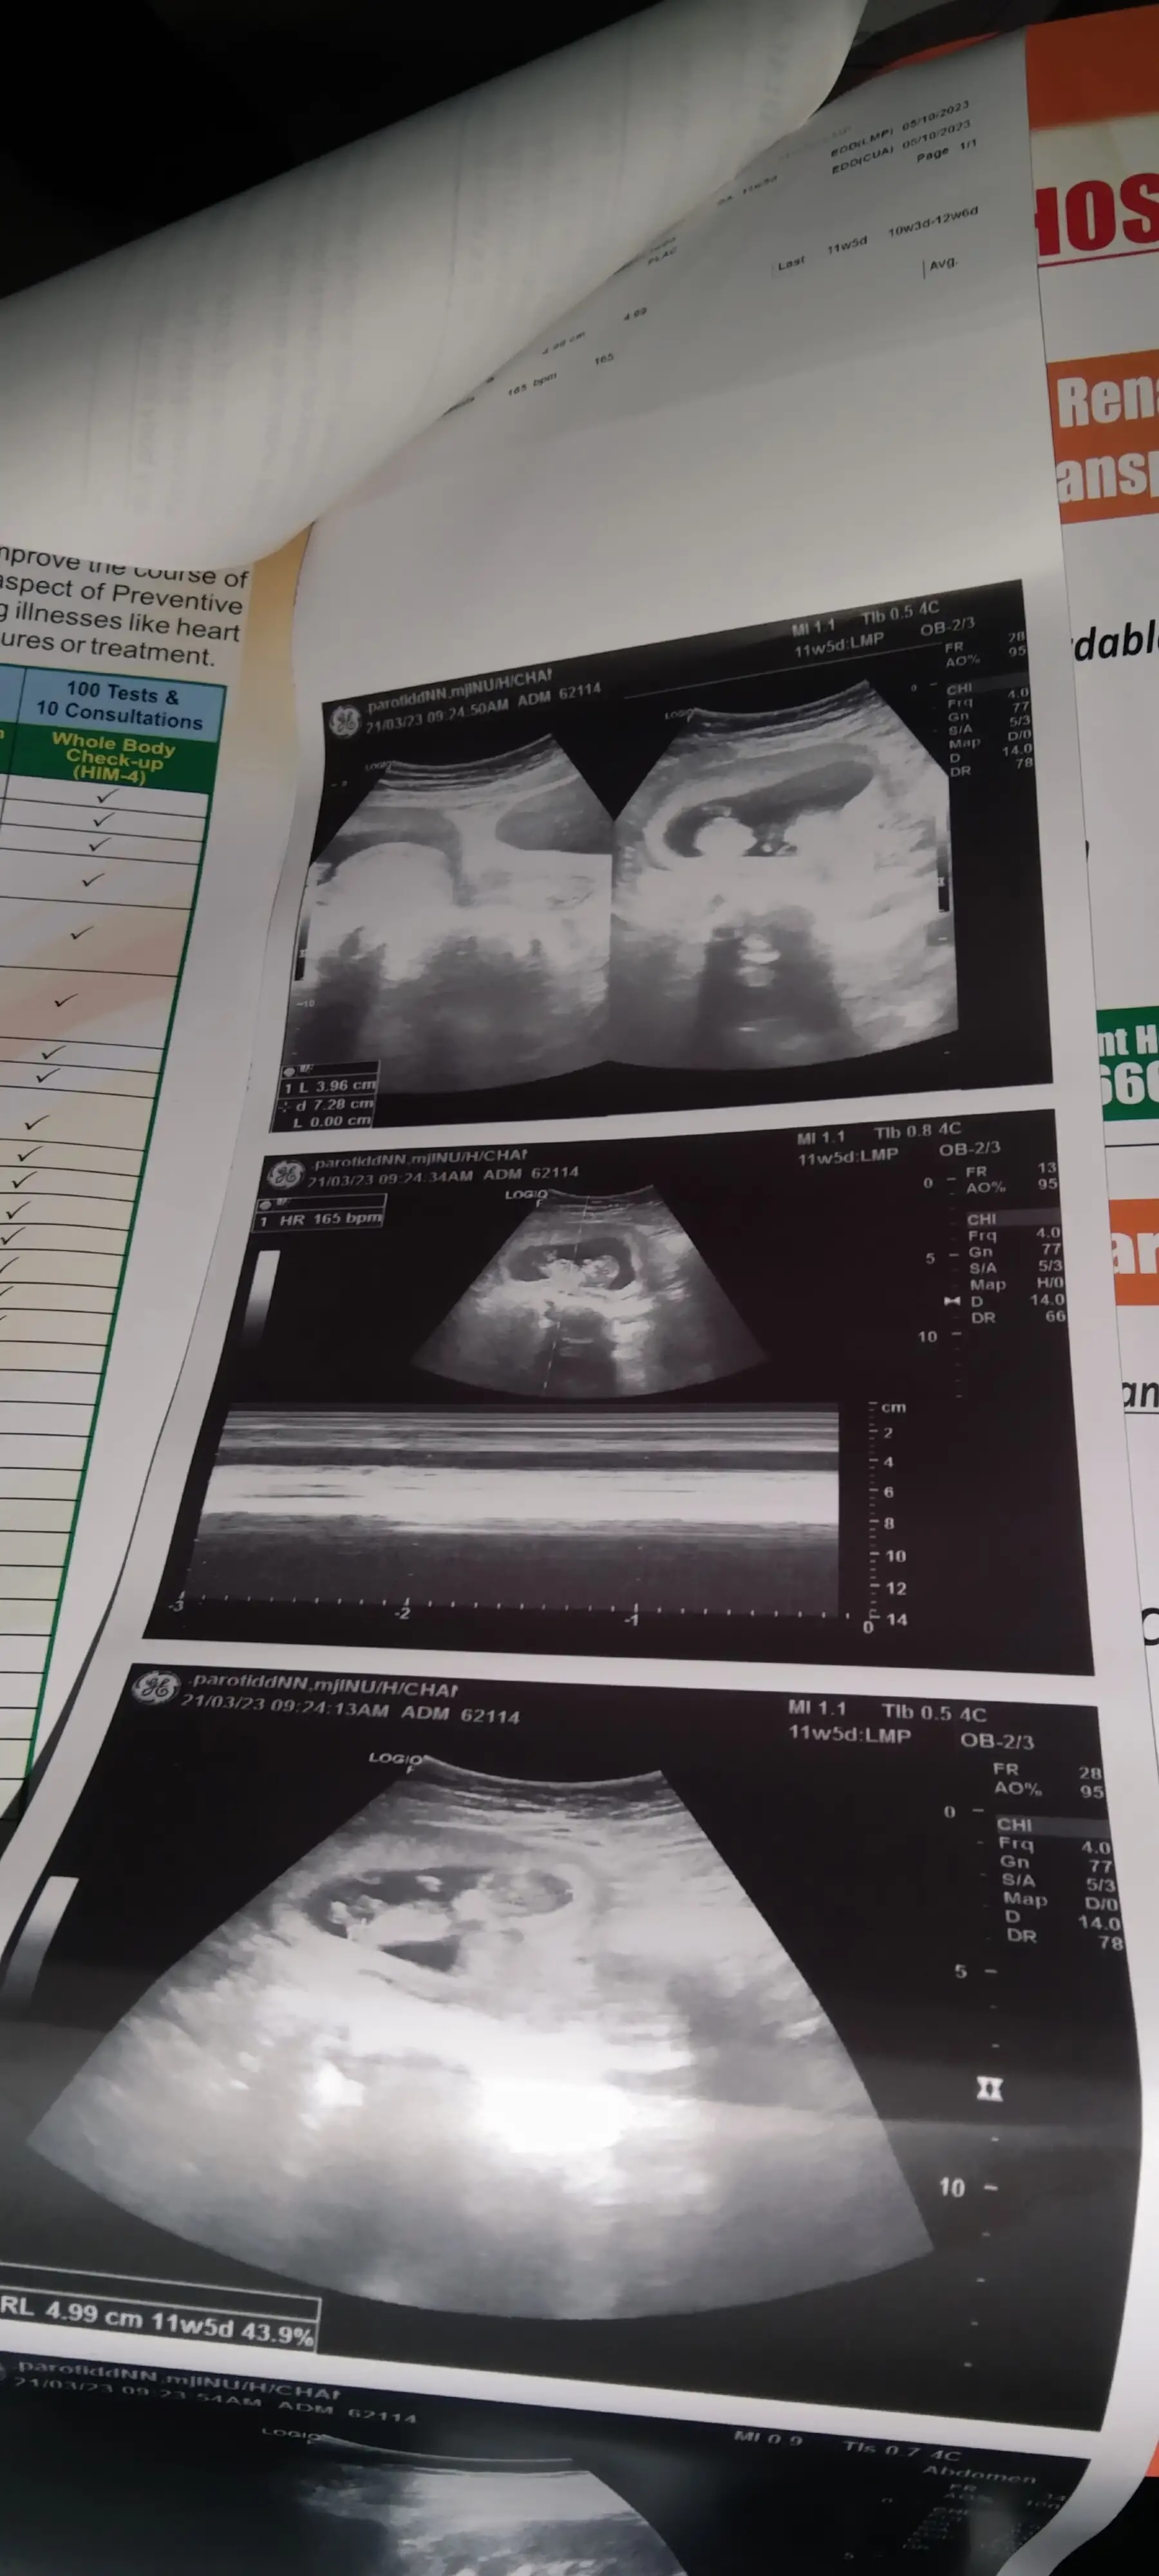

Q: Please mujhe batayen ye normal h sab.

A: Dear uh apne 11 weeks p krwye h ? ... See more

A: Scan se hume nhi samjhega report attach karo ... See more